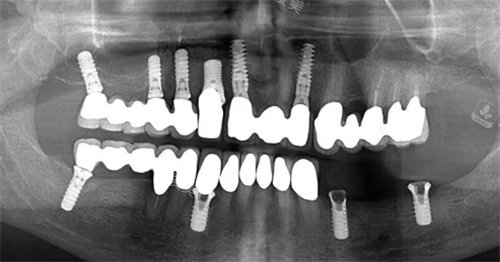

其次,牙博士口腔医院拥有先进的医疗设备和设施。

医院引进了国内外先进的医疗设备,配备了全套的口腔医疗设施,满足了诊疗过程的较准性和靠谱性,为患者提供了比较好的治疗方案和服务。